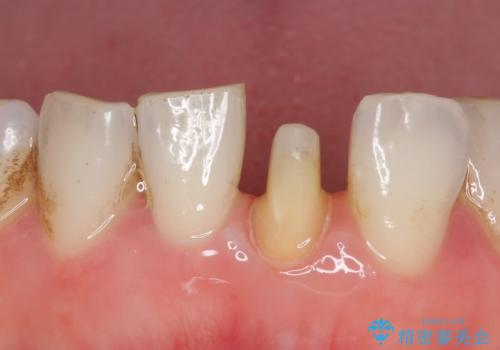

- 下顎前歯が茶色いのが気になるのでセラミックで治療したいといらっしゃった方の症例です。

再根管治療後、オールセラミッククラウン(スペシャル)による補綴を行いました。